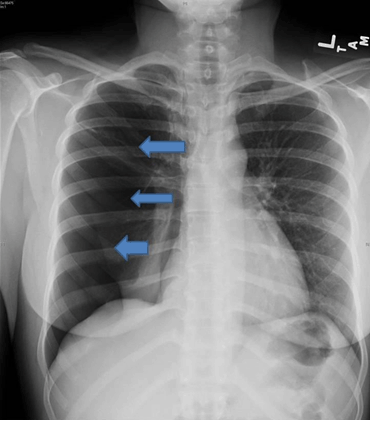

A 34-year-old Hispanic female non-smoker with no significant past medical history stated that she had been having pain in the scapula four days ago which was associated with shortness of breath. She described the pain as a sharp, constant, radiating to the front and back of the right side of the chest. The patient also stated that shortness of breath is associated with chest pain and dry cough. She was diagnosed with pneumonia by her primary medical doctor and she was prescribed antibiotics and pain medications which did not help her. She gave a history of spontaneous pneumothorax on her right side six months ago. She denied any fever, chills, nausea, and vomiting but stated that the pain gotten progressively worse. She did not have a history of tuberculosis or endometriosis. She had breast lifting seven years ago. Her last menstrual period was three days ago. She had three abortions which were induced and she has two babies. On physical examination, she was in mild respiratory distress and vital signs were temperature 98°F, blood pressure 127/58 mmHg, pulse 84/min, respirationrate 20/min, and PO2 96% on 2 litre/minute of oxygen per nasal canula. Lung examination revealed decreased air entry on the right side and decreased breath sounds on the right side. Rest of the physical examination was unremarkable. Laboratory data showed white blood cell count 10.4x103/mL, hemoglobin 13 g/dL, hematocrit 41%, platelets 343x103 K/uL, neutrophils 68%, lymphs 21%, BUN 8 mg/dL, creatinine 0.7 mg/dL, calcium 9.4 mg/dL, albumin 4.4 g/dL, total protein 6.7 g/dL, sodium 137 mmol/L, potassium 3.9 mmol/L, chloride 99 mmol/L, CO2 26 mmol/L. Chest X-ray showed 90% of pneumothorax (Figure 1). She was admitted and emergency right closed thoracostomy drainage done and mechanical pleurodesis was performed. Alpha 1 antitrypsin later came to be 106.00 IU/mL (90–200 IU/mL). Patient was diagnosed with catamenial pneumothorax. She was discharged home and has remained free of recurrence six months after re-treatment.

Figure 1: Chest X-ray showing 90% of pneumothorax on the right side.